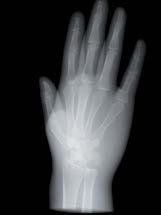

L’innovazione e la sicurezza sono due dei valori perseguiti dallo Studio Braconi a Terni, un punto di riferimento nell’ambito della radiologia 3D ortopedica grazie alla presenza del macchinario Newton 5G XL: si tratta dell’unico apparecchio nel Centro Italia che permette di eseguire una perfetta diagnostica per immagini in ortopedia e per la cervicale, oltre per le piccole articolazioni come seni paranasali, orecchie, colonna cervicale, gomito, polso, mano, ginocchio, caviglia e piede.

Nell’ambito della radiologia 3D ortopedica, il centro diagnostico utilizza il nuovissimo macchinario NewTom 5G XL, in grado di individuare con la massima precisione la presenza di fratture o lussazioni delle articolazioni, controllare la corretta guarigione di una frattura, valutare una lesione o una ferita causata da infezione, artrite o crescita anormale dell’osso.

Se con la radiologia tradizionale era necessario eseguire scansioni multiple, la novità introdotta dal macchinario NewTom 5G XL risiede nella capacità di fornire immagini ad alta risoluzione in un’unica scansione, mostrando nitidamente i dettagli delle articolazioni degli arti superiori e inferiori. Inoltre, a differenza della tecnologia 2D, la radiologia 3D ortopedica permette di individuare immediatamente alcune patologie come quella del metatarso, la quale richiede un allineamento visivo dedicato o una diagnosi delle micro fratture ossee.

Un altro valore aggiunto che rende la radiologia 3D ortopedica uno strumento fondamentale nell’ambito della diagnostica per immagini attuale è la bassissima dose di radiazioni emesse: infatti, la tecnologia CBCT garantisce una dose fino a 10 volte inferiore rispetto al MSCT.